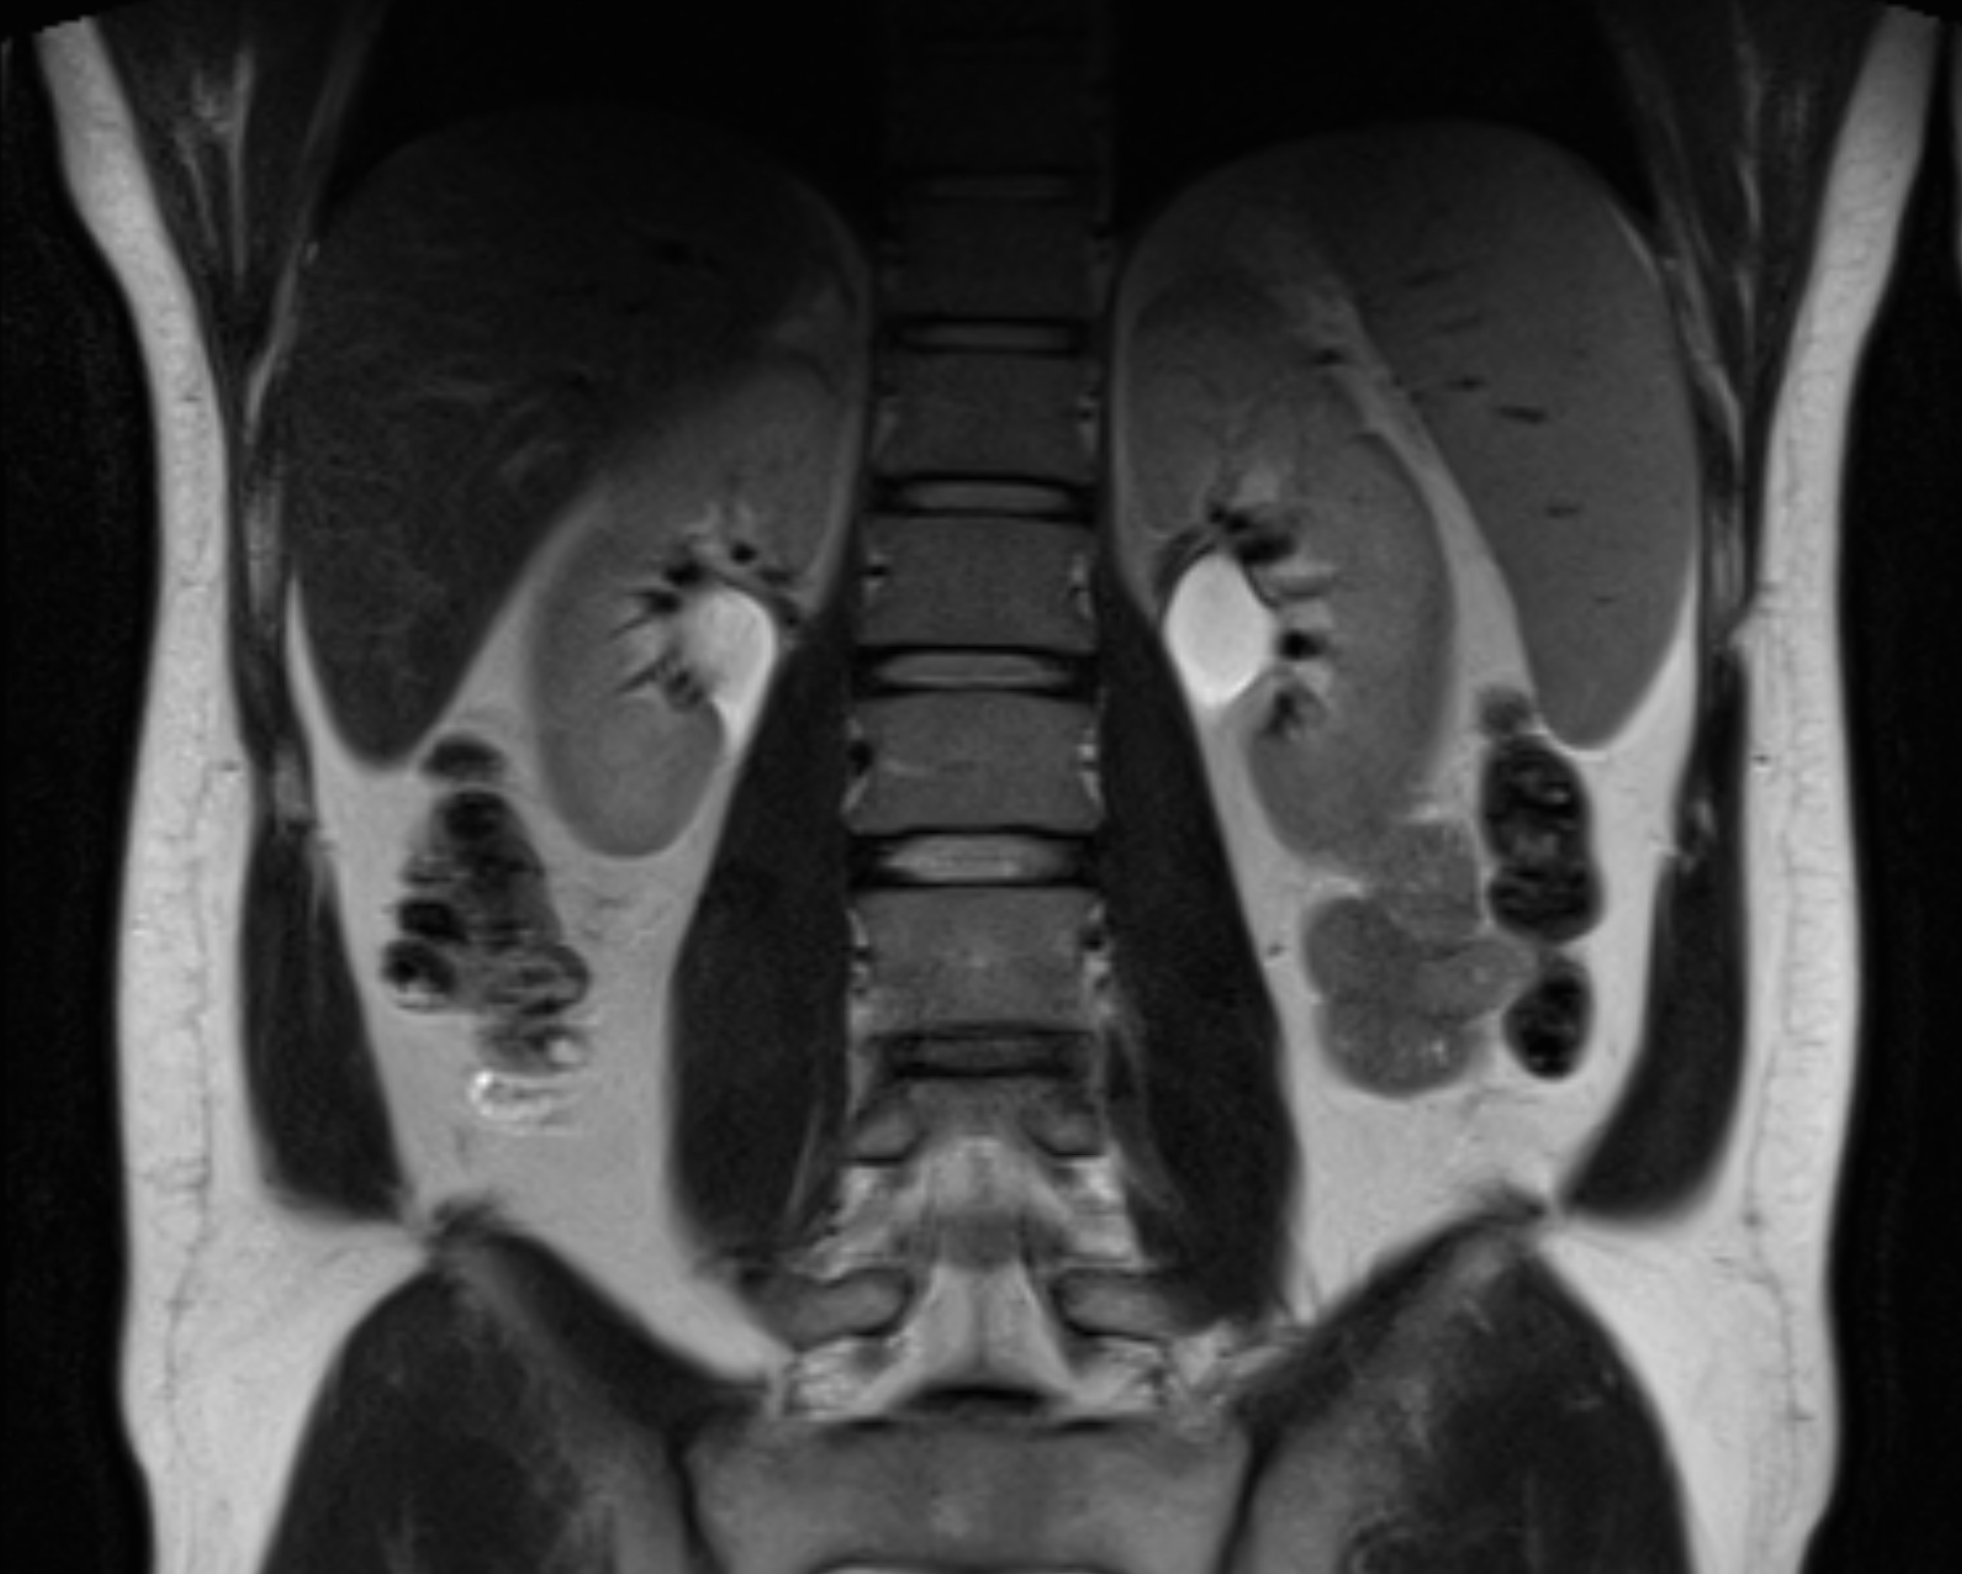

MRI is often used when the following conditions in the kidneys are suspected

- Kidney cancer or tumor in the renal pelvis

- Simple or complex kidney cysts

- Hydronephrosis (fluid accumulation due to outflow obstruction)

- Urinary tract stones (stones) in the upper urinary tract

- Pyelonephritis or other inflammation of the kidney

- Changes after surgery or transplantation